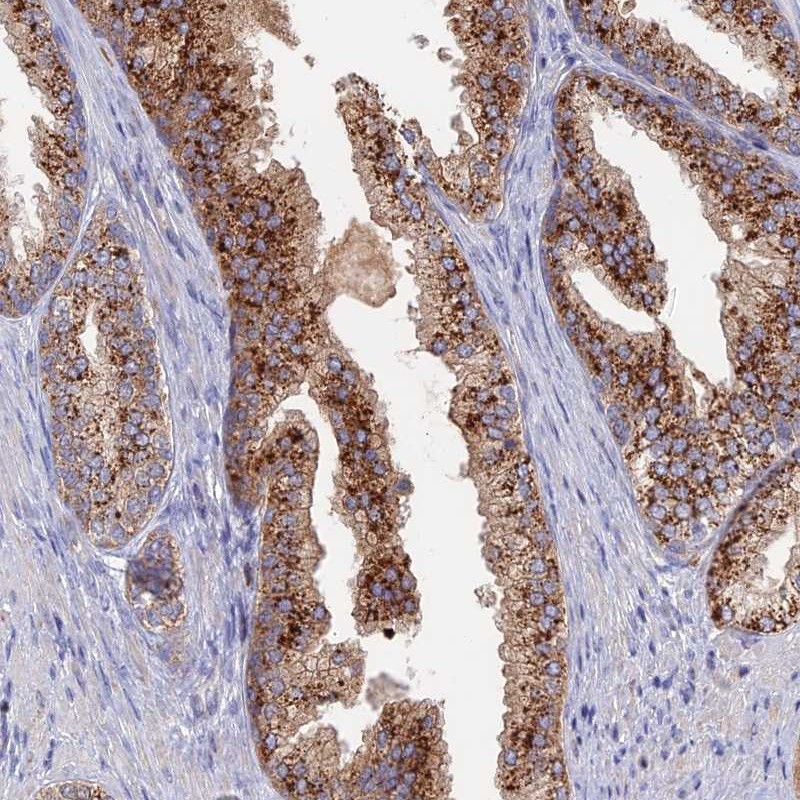

Immunohistochemical staining of human prostate shows strong cytoplasmic positivity in glandular cells.